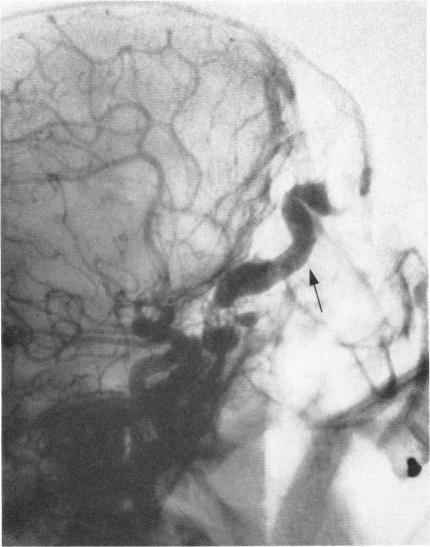

Arteriography and phlebography in the diagnosis of orbital affections.

Bull N Y Acad Med. 1968 Apr;44(4):409-30.